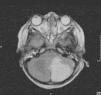

Niña de 5 años que sufre un accidente de tráfico por impacto frontal, con signos de traumatismo externo abdominal y un nivel de conciencia fluctuante, con ventilación espontánea, sin reacción a estímulos dolorosos, con pupilas isocóricas normorreactivas, frecuencia cardiaca 85lpm, presión arterial sistólica 90–95mmHg. De forma brusca, presenta deterioro hemodinámico, con disminución de frecuencia cardiaca, aleteo nasal y respiración bucal, siendo intubada, con GCS 3, en situación de shock (fig. 1). En ecografía abdominal se observa abundante cantidad de líquido libre, requiriendo resección quirúrgica urgente de 2 segmentos de intestino delgado por perforación y desgarro del meso. Una vez estabilizada, se realiza TC cerebral y de columna cervical, objetivando infarto cerebeloso izquierdo y fractura-distracción de C7, con invasión de canal. Ante la sospecha de lesión medular se realiza una RM de columna cervical (fig. 2) con una fractura horizontal de la porción inferior de C7 con extensión y separación de elementos posteriores y pseudomeningocele. Se asociaba sección completa medular en la unión C7-D1, con disección de la arteria vertebral izquierda e infarto cerebeloso en territorio de la arteria cerebelosa posteroinferior izquierda (fig. 3). A las 48h, la paciente desarrolló un cuadro de distress respiratorio agudo y midriasis bilateral arreactiva, observando en TC cerebral un aumento del efecto masa del infarto cerebeloso e hidrocefalia triventricular, con herniación transtentorial, concluyendo con muerte encefálica confirmada en arteriografía cerebral.